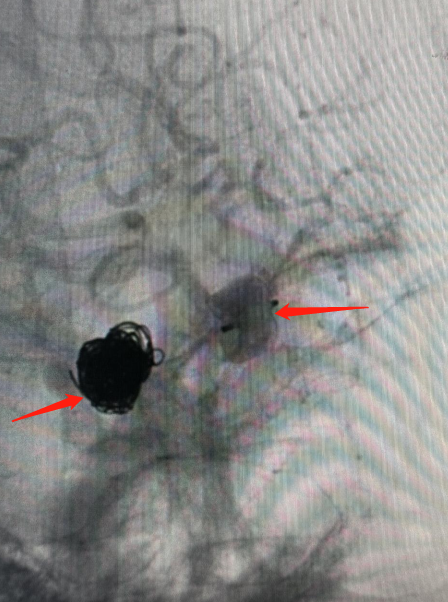

左侧箭头区域为一期手术(单纯弹簧圈栓塞治疗)

右侧箭头区域为二期手术(WEB治疗)